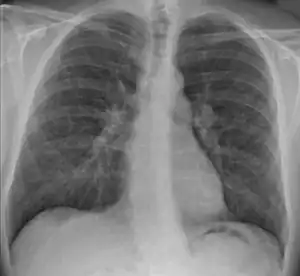

Sarcoidose é uma doença caracterizada pela formação de agregados anormais de células inflamatórias denominados granulomas.[2] A doença tem geralmente início nos pulmões, pele ou gânglios linfáticos.[2] Ainda que menos comum, pode afetar os olhos, fígado, coração e cérebro.[2] No entanto, é possível afetar qualquer órgão.[2] Os sinais e sintomas dependem do órgão envolvido. Na maior parte dos casos não se manifestam sintomas ou os sintomas são apenas ligeiros.[2] Quando afeta os pulmões podem ocorrer sibilos, tosse, falta de ar ou dor no peito.[3] Em alguns casos verifica-se síndrome de Löfgren, caracterizado por febre, aumento de volume dos gânglios linfático, artrite e uma mancha na pele denominada eritema nodoso.[2]

O acompanhamento dos pacientes requer a realização de exames de espirometria e radiografia de tórax periodicamente, ou seja, de 3 em 3 meses, ou de 6 em 6 meses.